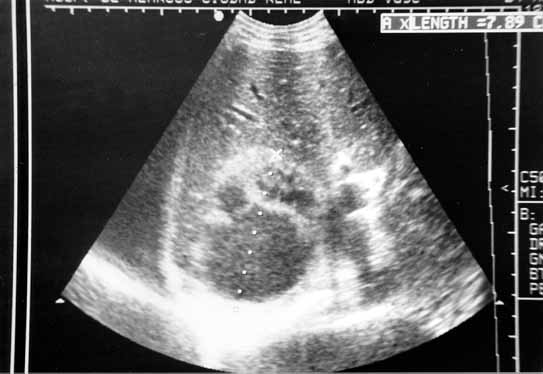

Figura 4: Caso 2. Ecografía de un tumor quístico heterogéneo de 7,89 cm de longitud, que está encima del polo superior del riñón derecho.